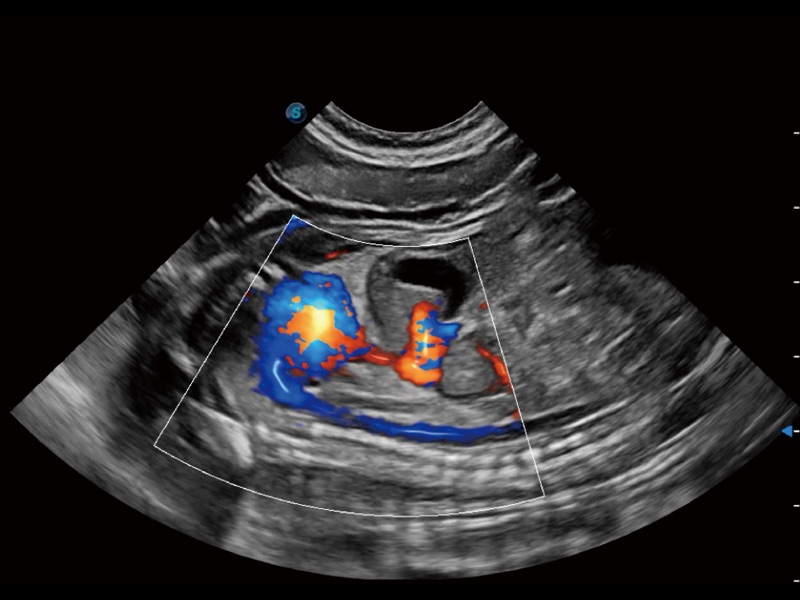

优异的基础图像

(犬)左室长轴血流

(犬)胎儿主动脉弓立体血流